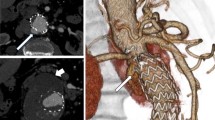

VRT overlay provided the projection of the target vessel on its entire length associated with target ostia vessel landmark represented as a ring (Fig. 1). It was used to select the optimal C-arm angulation during endovascular navigation. The generated 3D road map was synchronized with the C-arm/table positions in order to provide live update and to match the 2D-fluoroscopy at any C-arm/table angle, position and magnification. The image fusion accuracy was assessed at the beginning of each intervention with the control of the correct registration between the two image sets when the catheter was placed into the left renal artery.

This is a case of an in situ laser fenestration for two target vessels (superior mesenteric and right renal arteries); in this case, landmarks were placed at the ostia places of the celiac trunk, the superior mesenteric artery and the right renal artery. (The left kidney was atrophic and non functional.) First, the Aptus catheter was placed in front of the superior mesenteric artery based on image fusion coronal and sagittal views and the guide wire was placed into the target vessel after perforation, here the superior mesenteric artery (A). A cutting balloon was placed to enlarge the hole (B) followed by a balloon dilatation. A long sheath was placed into the target vessel (C) before the stent placement (D) and deployment (E). The Aptus catheter was then placed in front of the right renal artery on frontal and sagittal views before perforation (F)